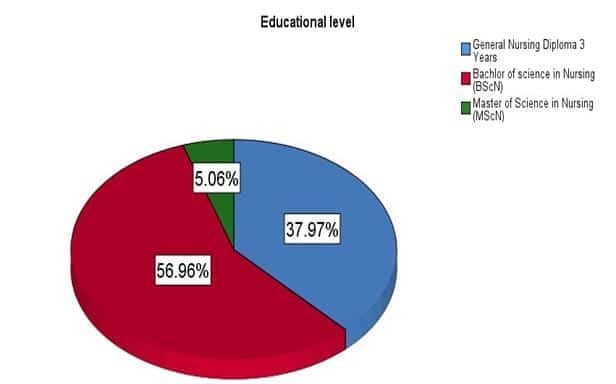

Knowledge, Attitude and Practice of Critical Care Nurses Regarding Infection Control Standard Measures at Saidu Group of Teaching Hospital

Background: Nosocomial infections are common in hospitals. Around the globe, these hospitals have acquired infections leading to adverse incidents at...Read More